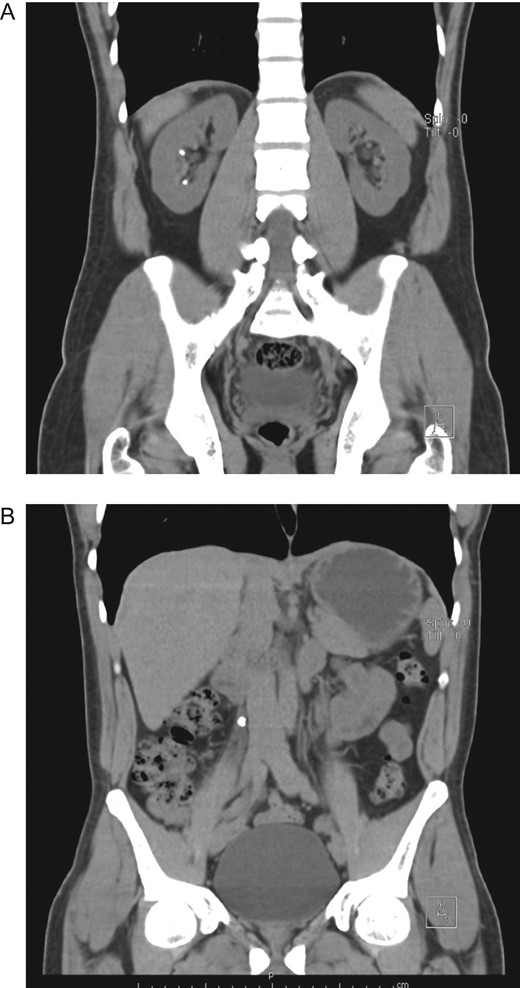

Urologist consultation was required and he underwent ureteroscopic lithotripsy without complications, the ureteral stone was removed and a right double J-stent was placed. Afterward, ESWL was decided for the right nephrolithiasis. A total of 3000 shocks were delivered at a maximum power of 15 kV and a rate of 80 shocks per minute. After the therapy was completed, the patient was discharged without any apparent complication. Nonetheless, 12 h after ESWL, severe pain appeared in his right flank, thus he presented to the emergency room. On clinical examination, a dehydrated, tachycardic and hypotensive patient was encountered. Pain was discovered on his right flank without tenderness. A contrast-enhanced abdominal CT revealed a 9 × 6 × 4 cm3 subcapsular liver hematoma, with an estimated volume of 300 ml that involved almost the entire right liver, without an active contrast material extravasation (Fig. 2A–C).

(A) CT, showing double J-stent and hepatic hematoma. (B) Contrast-enhanced CT, revealing a subcapsular liver hematoma. (C) Contrast-enhanced CT, subcapsular liver hematoma without contrast material extravasation.